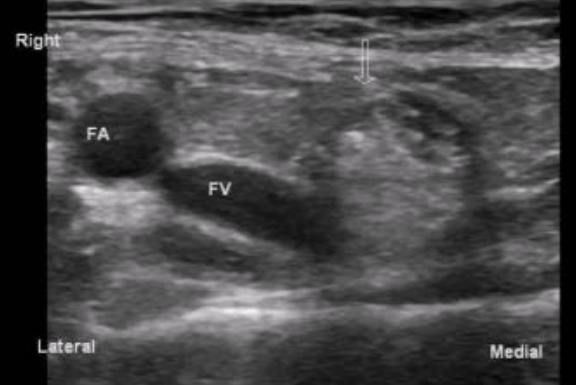

Femoral hernia

Protrusion of transversalis fascia - medial to CFV

More common in women (especially w/ pregnancy)

High risk of incarceration and strangulation

Because they are long w/ narrow neck